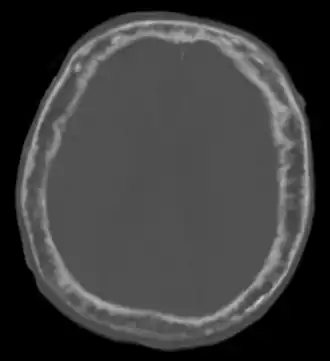

Elle est caractérisée par l'hypertrophie et la déformation de certaines pièces osseuses, principalement le bassin (près des 3/4 des atteintes), le crâne (40 % des atteintes), le rachis lombaire (près de la moitié des atteintes) et les os longs[4]. On peut retrouver des signes vasomoteurs, tels qu'une chaleur, une rougeur de la peau sus-jacente.

L'aspect radiologique est typique avec une déformation des os comprenant des zones déminéralisées et des zones de condensation.

Le cas Beethoven

Bien que cette hypothèse soit controversée[32], Beethoven pourrait avoir été atteint de la maladie de Paget selon une autopsie faite à Vienne le par Karl Rokitansky qui a décrit une voûte crânienne uniformément dense et épaisse et des nerfs auditifs semblant anormaux[33].

Il souffrait de déformations compatibles avec la maladie osseuse de Paget : sa tête semble avoir continué à grandir à l'âge adulte (à la fin de sa vie, il ne rentrait plus dans son chapeau, ni dans ses chaussures), son front est devenu proéminent, sa mâchoire était grande et son menton saillant. Il est possible et probable qu'une compression de certains nerfs crâniens, notamment le nerf auditif (huitième nerf crânien) ait affecté son ouïe. C'est l'une des hypothèses rétrospectivement apportée pour expliquer son humeur et sa surdité (qui a débuté vers 28 ans et était totale à 44 ans)[33] ; l'autre, qui n'est pas exclusive de la première, étant le saturnisme, sur la base de mesures du plomb contenu dans des mèches de cheveux qui ont été conservées. Ce serait cependant une cirrhose du foie d'origine alcoolique qui l'aurait tué.